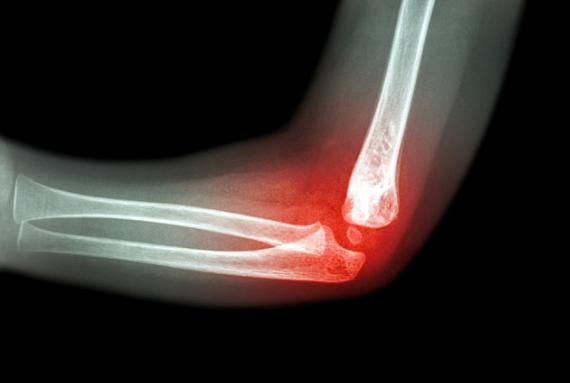

高度活動的炎症。以“28個關節-血沉”為主要指標的疾病活動度評分是臨床常用的評價指標之一。如果評分>5.1且影像學提示關節及周圍炎性活動表現,則提示病情仍處於高度活動狀態,是“難治”的主要特徵。

如果患者可以早發現、早期規範治療,並進行定期監測,絕大部分類風溼關節炎患者可達到治療目標。如果失去最佳治療時機,已出現關節破壞、畸形,或內臟受累,治療效果便會大打折扣,而且藥物選擇開始受限,部分患者會發展至難治性類風溼關節炎。